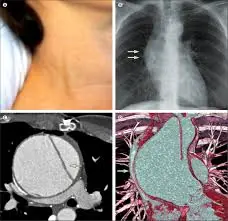

Jugular vein distension (often abbreviated JVD) refers to the visible bulging of the jugular veins in the neck. These veins normally carry blood from the head back to the heart, and when they appear dramatically swollen or “popping” out, it can signal that something is wrong with the body’s circulatory system.

The jugular veins—particularly the internal jugular vein—run down the sides of the neck and return blood to the heart via the superior vena cava. Under normal conditions, these veins are not prominently visible. However, when pressure builds up in the heart or large veins, blood can “back up” and cause the neck veins to bulge outward.

Medical professionals often assess jugular venous pressure (JVP) by observing how far above a reference point (like the sternum) the distension extends. A distension higher than about 4 centimeters above the sternal angle is commonly considered abnormal and potentially concerning.

Massive jugular distension is not a disease itself. Rather, it is a clinical sign — a visible clue that something deeper may be affecting heart or circulatory function. In many cases, it points to conditions that affect how the heart pumps or receives blood.